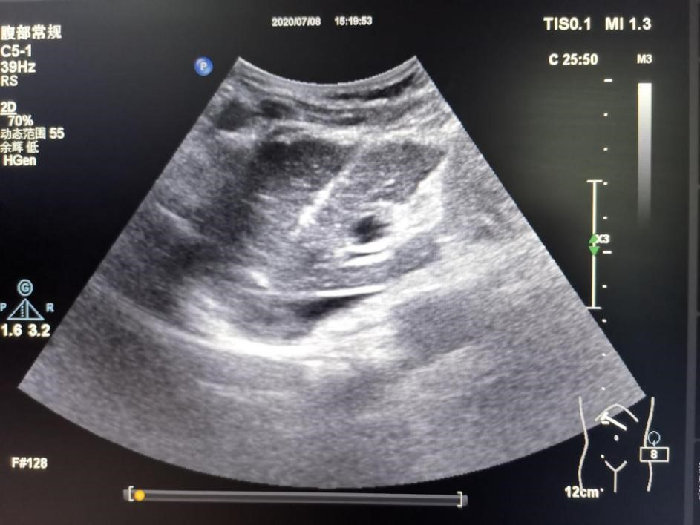

箭头所指病灶紧邻膈肌及下腔静脉

7月8日下午进行手术,超声诊断科主任医师肖迎聪、骆会婷指导,超声造影再次锁定病灶,采用基础麻醉加局麻,王涛徒手进针,当针刺入肝脏时仿佛空气都凝固了,针尖经过肝静脉时用特殊手法顺利避开,缓慢稳定的刺入病灶内,此时消融针已进入肝脏10cm。固定消融针后,再次进入PTC针,由于病灶较小,操作空间更小,第二根针的进入更难,王涛精准操作,成功的将第二针布到肿瘤边缘与下腔静脉的微小间隙当中。开始消融,大家的眼睛都紧盯膈肌与下腔静脉,当肿瘤瞬间变化时及时停止消融,同时PTC针推入2ml聚桂醇立刻拔针,术后即刻超声造影评估消融范围,显示无灌注区完全覆盖肿瘤,下腔静脉、膈肌以及肝静脉未见异常,手术成功。